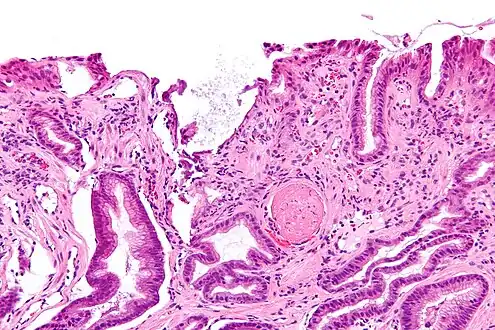

GAVE is characterized by dilated capillaries in the lamina propria with fibrin thrombi. The main histomorphologic differential diagnosis is portal hypertension, which is often apparent from clinical findings.

GAVE is usually diagnosed definitively by means of an endoscopic biopsy.[6][7][10][20] The tell-tale watermelon stripes show up during the endoscopy.[7]